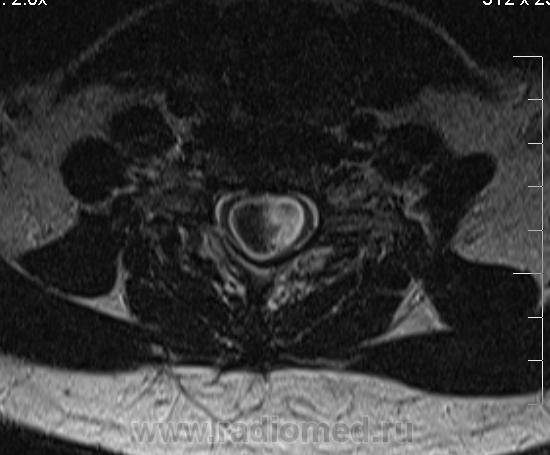

Сирингомиелия шейно-грудной локализации? Аномалия Арнольда-Киари I. Платибазия.

здоровенная сирингогидромиелитическая киста (по видимому, "высокого давления"), мальформация Киари 1.   также имеются признаки внутренней окклюзионной гидроцефалии.